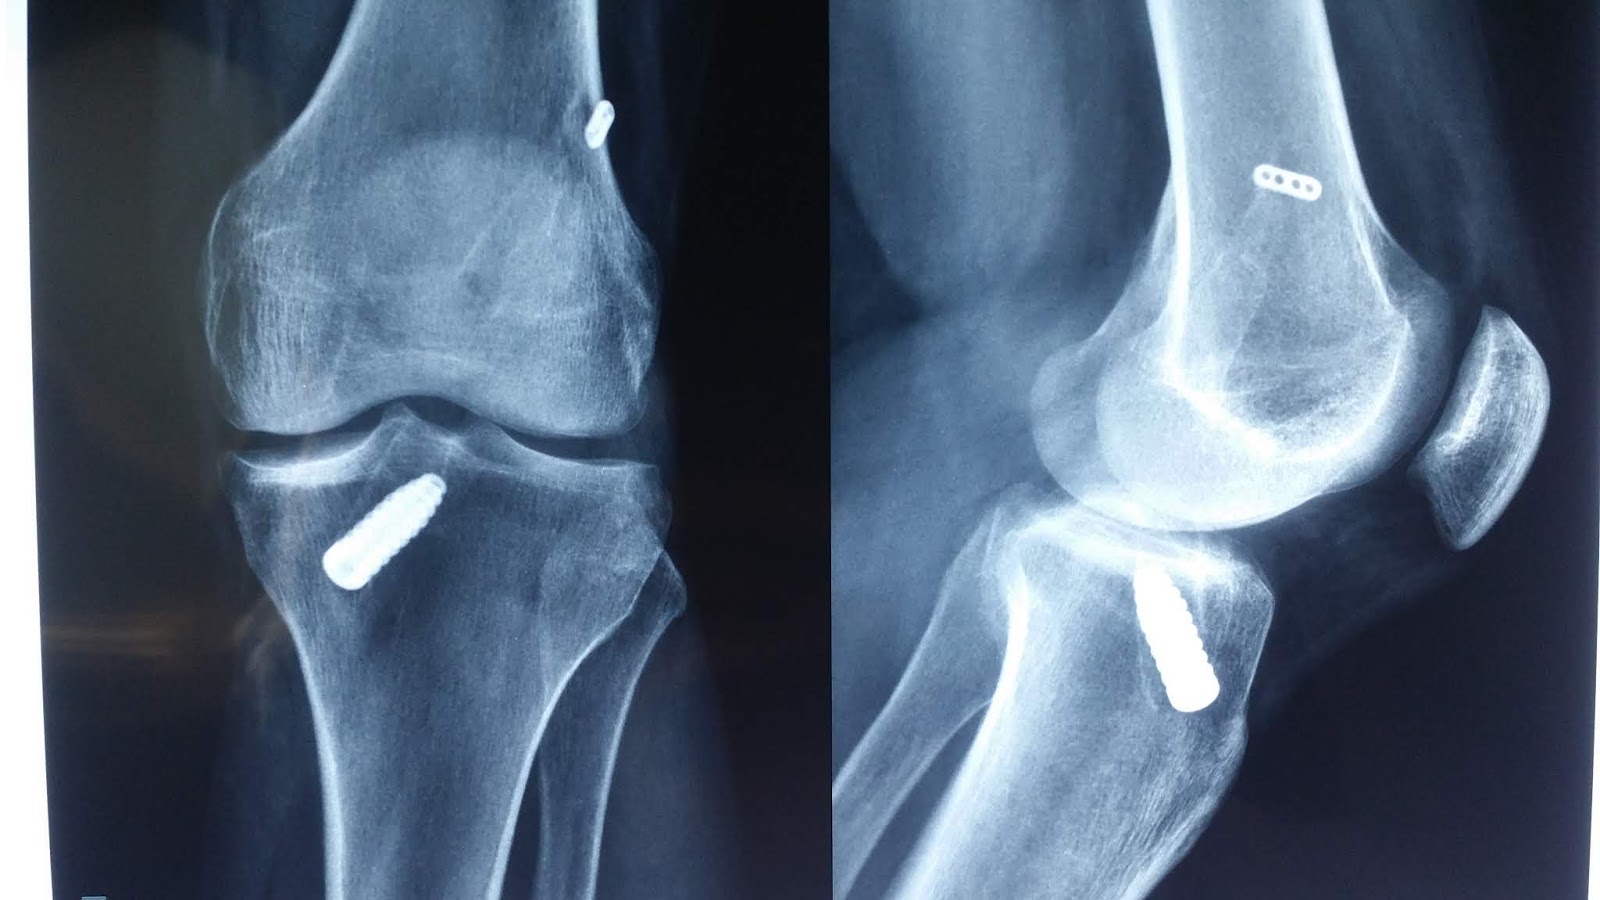

A cirurgia é concluída pela colocação do enxerto dentro do joelho para substituir o ligamento rompido. Por fim fixamos com parafusos, placas ou pinas a depender da preferência do cirurgião

Ilustração de um dos modos de fixação do enxerto

Rx mostrando um dos modos de fixação após reconstrução do LCA